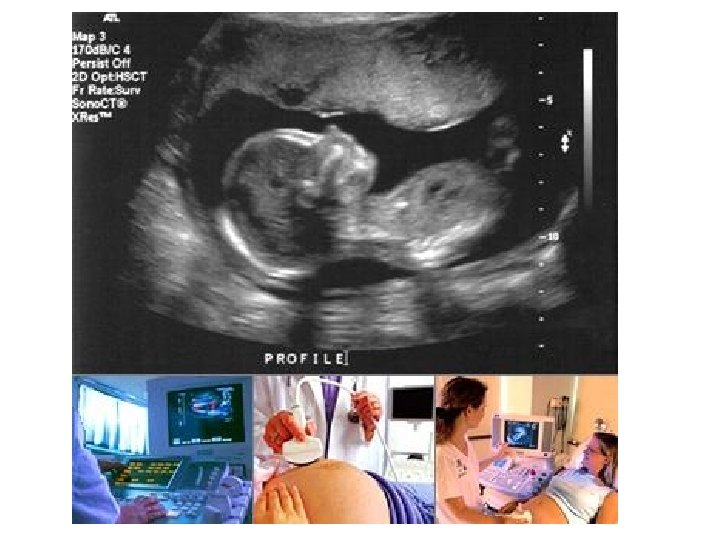

Career in Radiography Ultrasound (sonography) --uses high frequency sound waves

Ultrasound beam is transmitted and reflected – as special crystal at the end of the transducer can determine the type of tissue Determines depth 81

Uses SOUND WAVES (NOT X-RAYS) “real time” images 82

ULTRASOUND uses a technique similar to Navy SONAR to produce diagnostic images. 83

U/S & the “real thing” 87